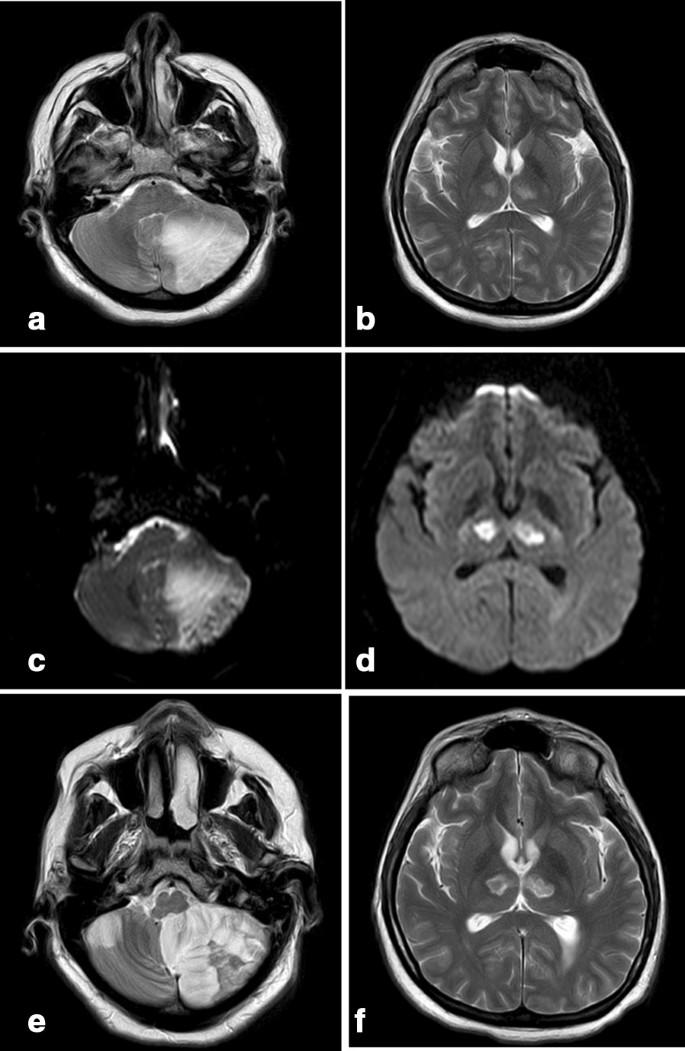

A brain MRI demonstrated an acute ischemic stroke with limited hemorrhagic components in the left cerebellum hemisphere and the left part of the vermis, and pressure on the 4th ventricle. Symmetric thalamic infarcts were also observed. On the 7th-day post-admission, mild deterioration with projectile vomiting was reported, and a new MRI was performed (Fig. 1). A new smaller acute ischemic stroke was found in the right cerebellum hemisphere. An MRI of the intra and extra-cranial vessels performed several days later did not reveal any vascular abnormalities.

T2-weighted MRI showing a large infarct in the left cerebellar hemisphere (a) and rounded areas with high signal alteration in the medial thalami, corresponding to a bilateral paramedian thalamic infarct (b). Diffusion-weighted MRI demonstrating the left cerebellar (c) and bilateral thalamic infarcts (d). Second magnetic resonance imaging (MRI) 8 days later (e, f), T2-weighted MRI showing a new cerebellar infarct in the cerebellum’s right hemisphere (e)